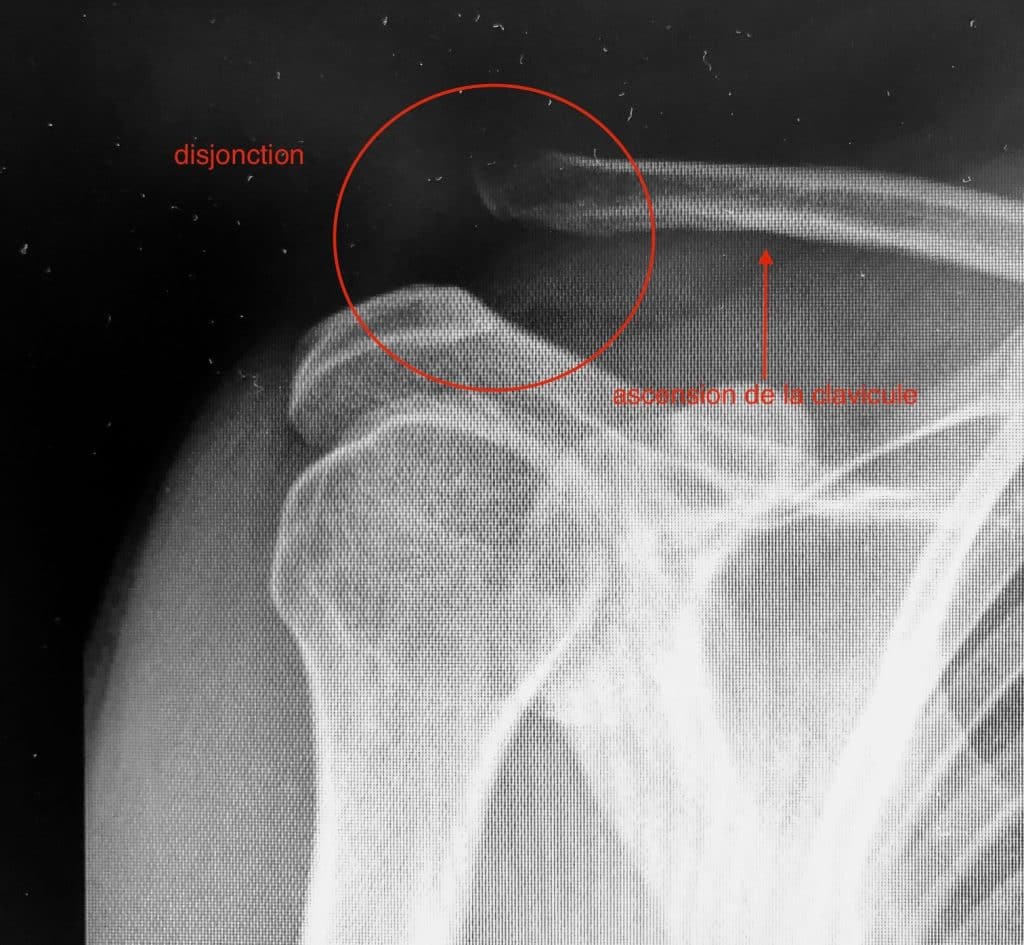

Traumatisme de l’acromio-claviculaire ou disjonction acromio-claviculaire

Suite à une chute sur l’épaule, ce traumatisme engendre soit une simple douleur avec ou sans bosse, soit une véritable luxation acromio-claviculaire avec ascension de la clavicule.

Disjonction acromio-claviculaire